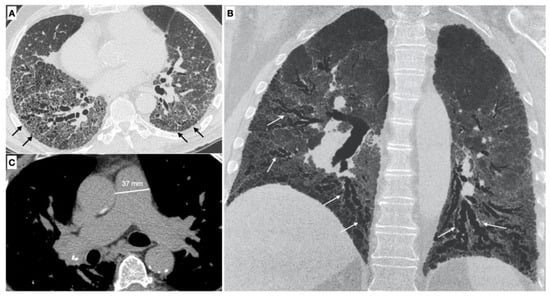

Parenchymal signs. There are different forms of pulmonary involvement in SSc. HRCT plays a central role in the diagnosis of ILD (interstitial lung disease), in recognizing the pattern of lung involvement and in providing information regarding the extension of the interstitial involvement [3] (Figure 2).

It is possible to distinguish two different phenotypes of patients with SSc based on the association between ILD and pulmonary hypertension: the first one occurs when PH is associated with ILD, the second one when PH is not related with the extension of the ILD [38]. The association of ILD and PH increase the mortality risk to five-fold in SSc-PAH [39].

Vascular signs. The pulmonary vascular involvement in SSc can cause PAH. Typical radiological findings are represented by a main pulmonary artery with a diameter equal of greater than 29 mm measured in a scanning plane of its bifurcation, this sign has a positive predictive value of 97%, sensitivity of 87% and specificity of 89% for the presence of PH [37,40,41].

Meanwhile a diameter of the main pulmonary artery that is greater than that of the ascending aorta (PA/AA > 1) is another vascular sign of pulmonary hypertension, with a appositive predictive value of 96% and a specificity of 92% [42].

Interstitial lung disease (WHO Group III of pulmonary hypertension). ILD is present in up to 90% of patients with SSc [43]. The most common ILD in the SSc patient is the NSIP pattern, characterized by a different degree of inflammation and fibrosis (cellular and fibrotic NSIP). The cellular NSIP pattern is characterized by the presence of ground glass opacities with a bilateral and symmetrical distribution; when fibrotic changes occur (fibrotic NSIP pattern), irregular septal thickening, bronchiectasis and bronchiolectasis can be recognized on HRCT as superimposed features on a background of pre-existing ground glass opacities [43]. The usual interstitial pneumonia (UIP) pattern is less common in SSc and this pattern is characterized by the presence of irregular septal thickening in the peripheral and subpleural regions of the lungs, honeycombing, traction bronchiectasis and pulmonary volume loss. This pattern has a worst prognosis and a faster progression [3] (Figure 3).

PH can be detected in patients with ILD, in particular in those patients with an extension of fibrotic changes greater than 20% of the lung volume [3], and this is an indicator of morbidity and mortality [3].

Figure 2. (A,B) Parenchymal signs: axial high resolution CT scan shows a fibrotic NSIP pattern due to the presence of diffuse irregular septal thickening (black arrows), bronchiectasis and bronchiolectasis on a background of diffuse ground glass opacities. Both lower lobes are symmetrically involved by these alterations. Bronchiectasis and bronchiolectasis (white arrows) are better visualized on the MinIP coronal plane reconstruction; (C) Vascular signs: a main pulmonary artery with a diameter greater than 36 mm measured in a scanning plane of its bifurcation is a sign of pulmonary hypertension.